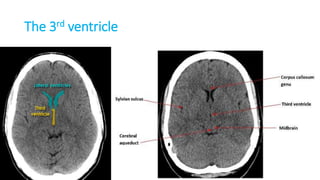

THE VENTRICLES

Ventricles

• Lateral ventricle

• Frontal horn

• Occipital horn

• Temporal horn

• Third ventricle

• Fourth ventricle

• Central canal

Foramen monoro

Aqueduct of Silvius

Interventricular foramina

(or foramina of monro)

The lateral ventricle

The frontal horn

The

occipital

horn

The temporal horn

The 3rd ventricle

The 4th ventricle

Foramen Luschka and Magendie